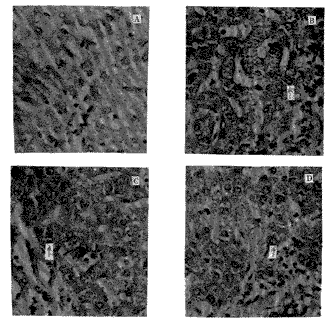

经细胞融合、筛选和克隆化,获得3株能稳定分泌抗人F蛋白mAb的杂交瘤细胞,命名为4F2,1G3和2B11。3株杂交瘤细胞培养上清中的mAb滴度为1×10-2~1×10-3;腹水中mAb的滴度为1×10-5~1×10-6。mAb的Ig亚类分别为IgG2(4F2),IgG1(1G3)和IgG1(2B11)。免疫组化的结果表明,3株mAb均能与肝细胞浆内容物结合,而不与血管上皮细胞及纤维组织相结合(图1)。

图1 3株抗人F蛋白mAb对正常肝组织切片的

免疫组化染色鉴定 (免疫过氧化物酶法×400)

注:A:阴性对照;B:4F2;C:1G3;D:2B11.